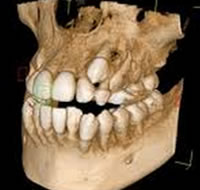

顎の骨の深い部分に埋まった状態の親知らずは、傾いた状態や横を向いた状態のものが多く、血管や神経が近接しており、本来抜歯が非常に難しい治療でした。

しかし、CTレントゲンにより3Dの画像で事前に分析、診断することで安全かつ正確な治療を行うことが出来ます。

そのため、難抜歯であっても短時間で治療を行えるようになり、患者様の負担も軽減されました。